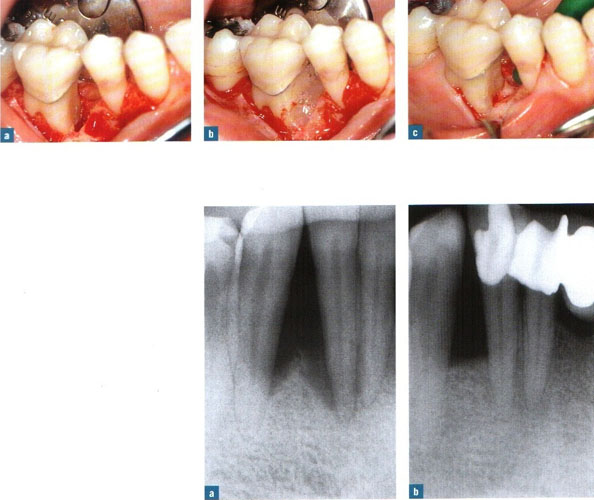

rejeneratif periodontoloji ameliyatı

ilerlemiş dişeti hastalığı sonucunda dişin içinde oturduğu kemik (alveol kemiği) iltihabi olaylar sonucu erimeye başlar ve belli bir süre sonra dişte sallanmalar (mobilizasyon) yer değiştirme görülür.

Ayrıca genel ve lokal dişeti abseleri oluşabilir. Bu sorunun tedavisinde dişetinin açılarak dişik kök yüzeyinin temizlenmesi, civardaki iltihaplı dokunun (granülanyon dokusu) temizlenmesi ve kliniğimizde uyguladığımız yöntemle, o boşluklara yapay kemik + minematriks proteini (Emdogain (R) ) uygulaması yapılarak 6-8 ay sonra operasyon bölgelerinde yeniden alveol kemiği oluşumu sağlanmakta ve bu yolla belkide çekilecek bir diş ağızda tutulmaktadır.

1) Dişeti cebinde azalma 2) Dişeti iltihaplarının ortadan kalkması 3) Ataşman (dişetinin yeniden dişe yapışması) kazancı da operasyonun başarısının kanıtı olarak ortaya çıkar.